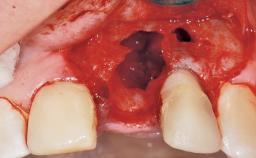

A 42-year-old female patient was referred to our clinic at the School of Dentistry of the University of São Paulo in November 2004, presenting a deficient restoration in the upper left central incisor. The clinical examination revealed no gingival retraction or any signs of gingival inflammation and, therefore, previous periodontal treatment was not considered. The patient presented a high lip line at full smile and a thin tissue biotype. This combination characterized a high-risk situation from an anatomic point of view, which required careful preoperative planning and cautious surgical execution.

Placement Protocol Immediate implant placement

Socket Integrity Sufficient, with intact bone walls

Bone Volume Sufficient, with intact walls